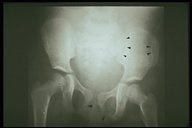

X-ray showed a fracture line on the ischium (arrow) and both pubic rami in a child with severe pelvic fracture and massive retroperioneal hemorrhage